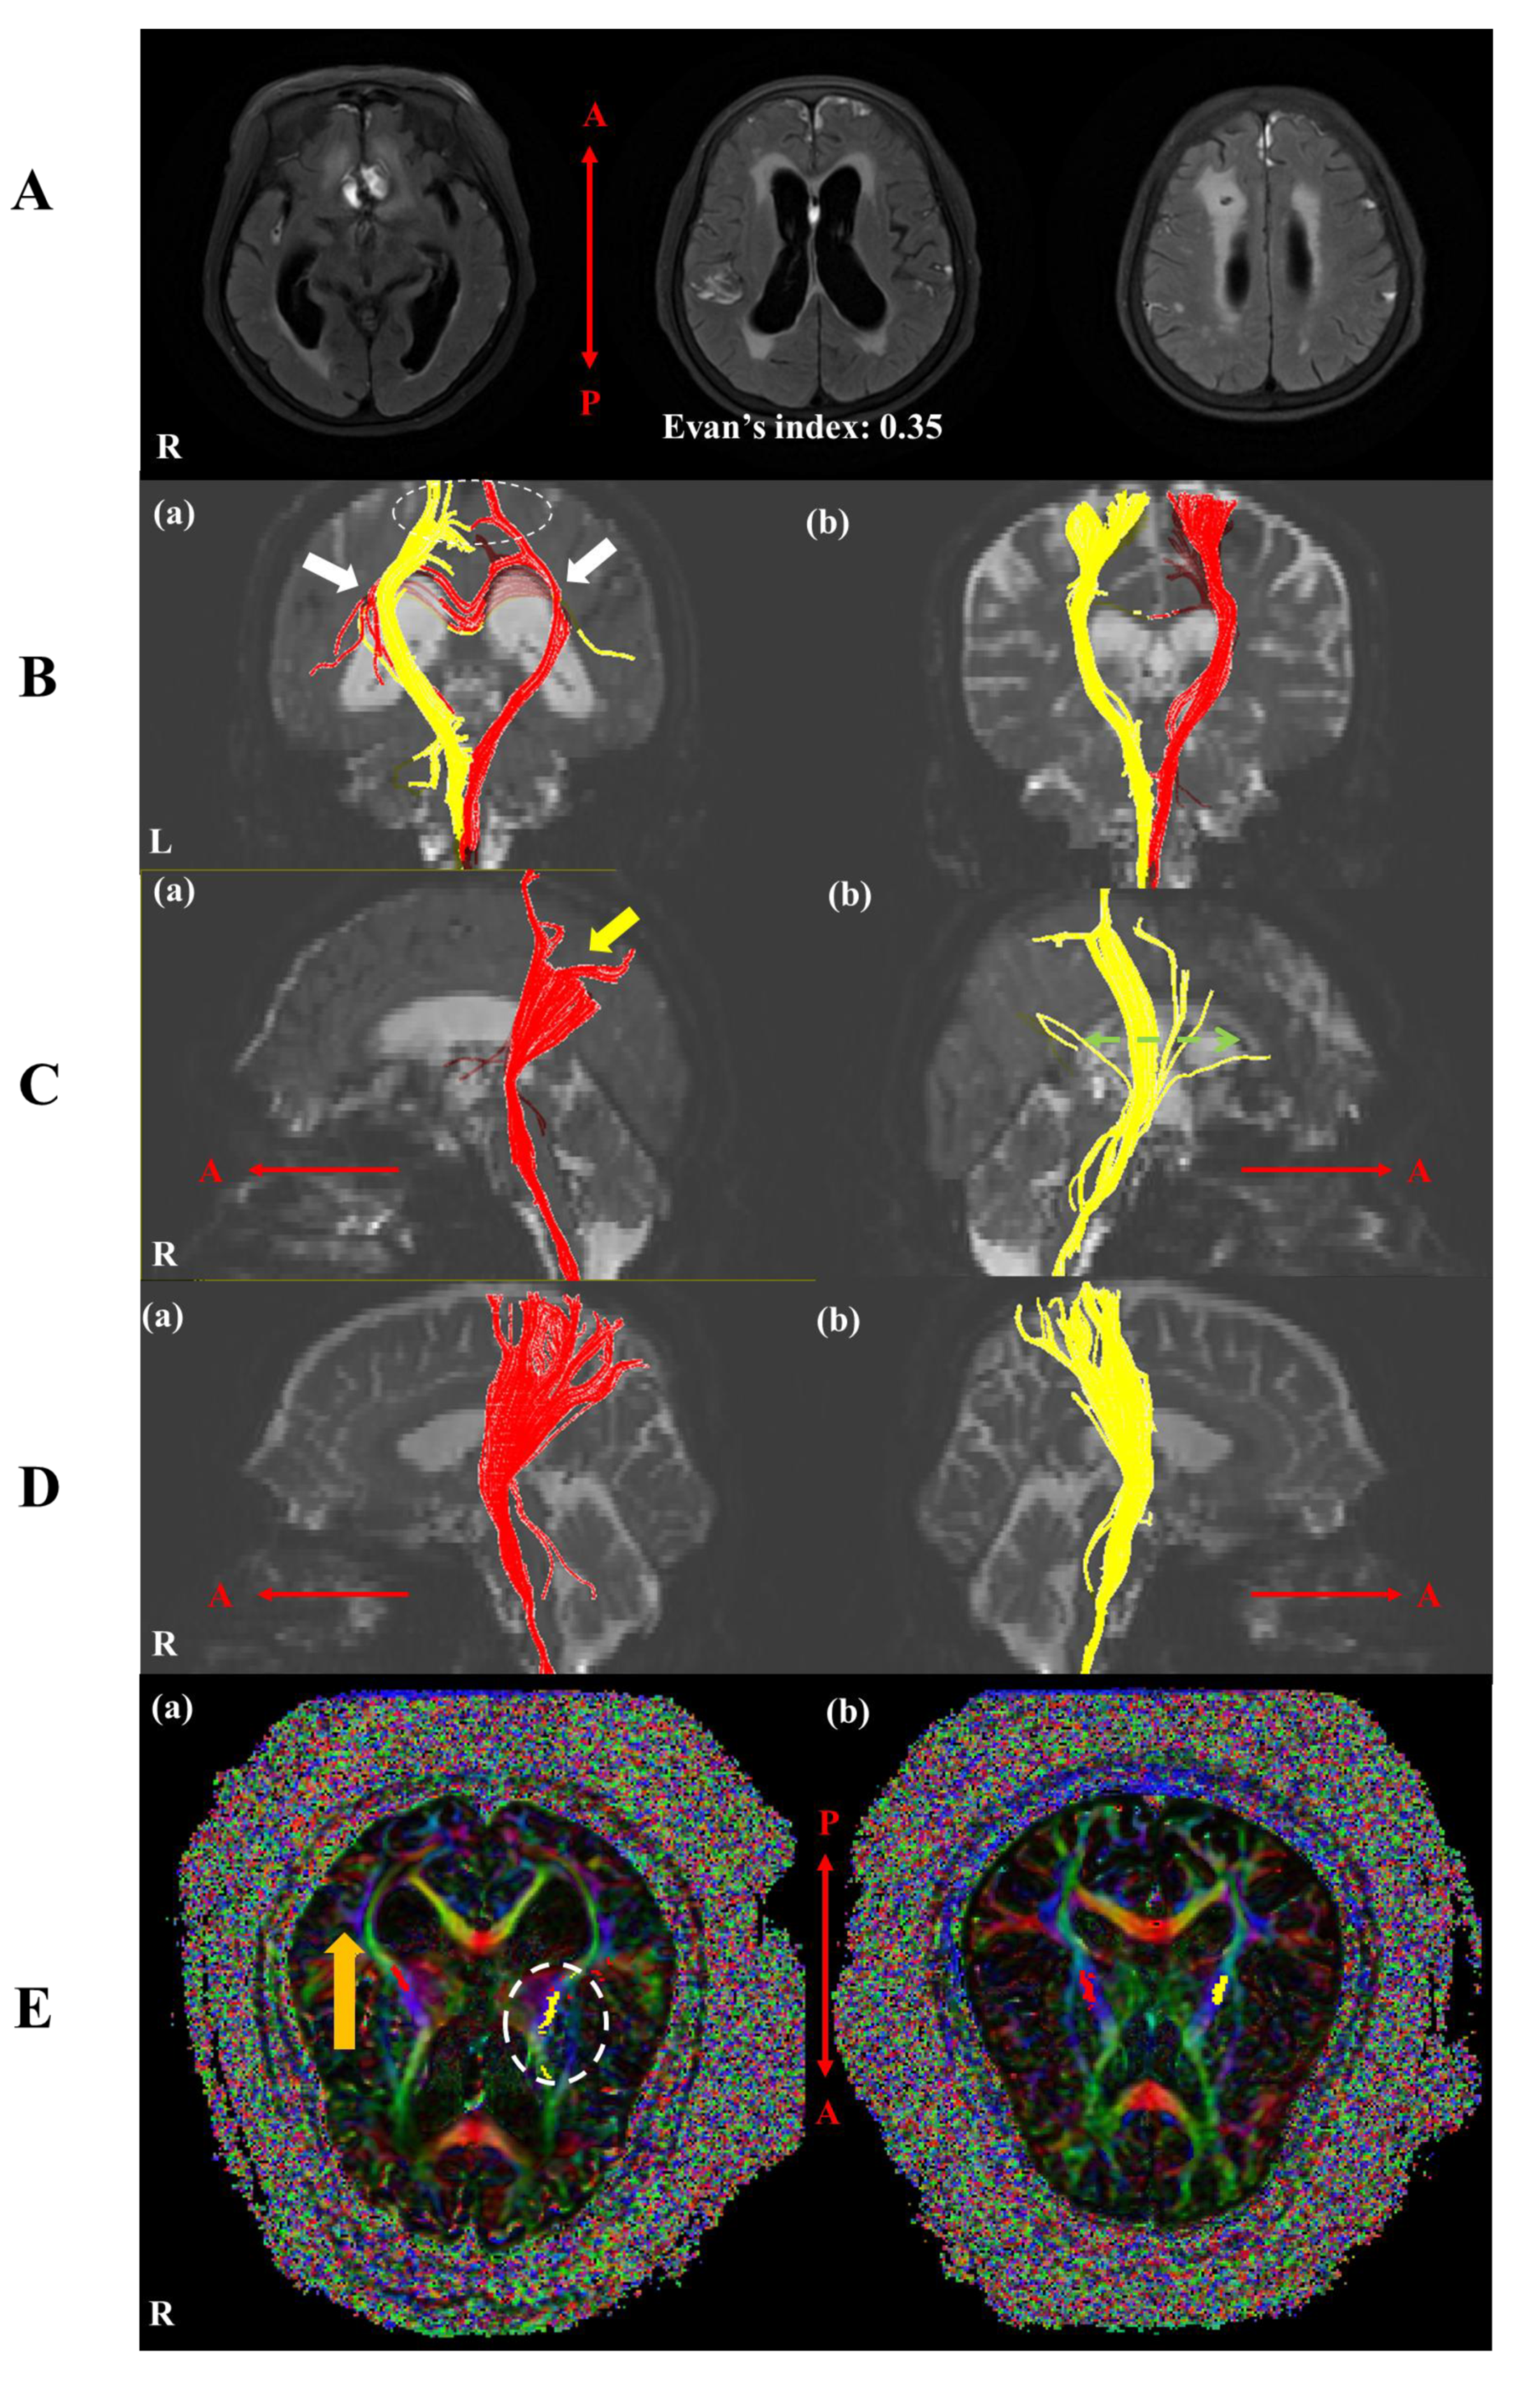

3. Diffusion Tensor Imaging